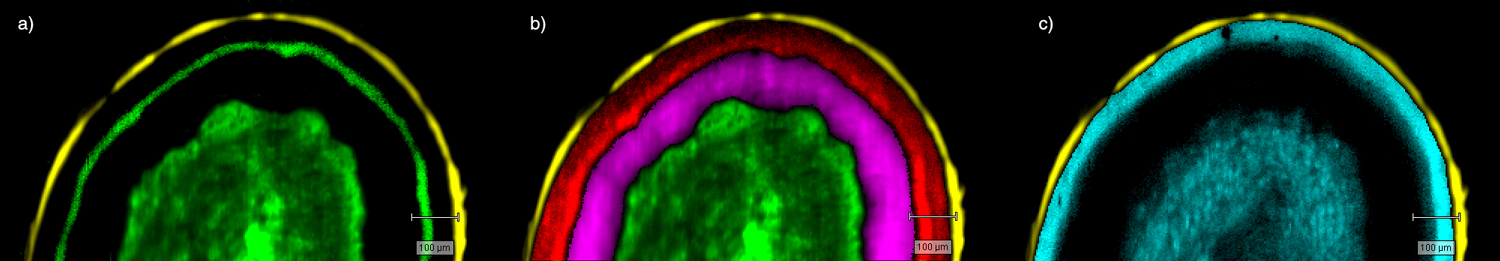

- Generate images of the formulations used in tablets, inhalers and nasal sprays at sub-micrometre spatial resolution

Rapidly generate images of your formulations with StreamLine™. This uses line focus illumination, allowing you to use higher laser powers without risk of sample damage, thereby reducing experiment times.

With the RA802 pharmaceutical analyser you can achieve imaging speeds of over 1500 spectra/s. It takes less than 2 minutes, from placing a standard tablet in the system, to generate a full, high resolution Raman image.

Generate images of formulations

Ensure your chemical images are representative; use Renishaw's StreamLine. You can change resolution to suit your domain size and, because Renishaw's WiRE software can cope with massive data files, you can analyse over the entire sample surface. Powerful Renishaw features, such as Slalom (to ensure the whole surface is sampled) and HD imaging (to get crisp clear images), provide all the options you need, whatever your formulation.